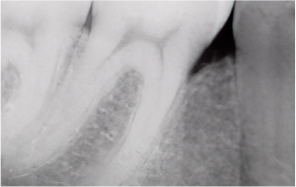

치주질환이란?

‘잇몸병’이라고 불리는 치주염은

잇몸과 잇몸뼈(치조골)를 파괴하는 대표적인 질환입니다.

초기에 단순히 잇몸이 붓고

피가 나는 수준에서 시작하지만,

방치하면 치조골이 점차 흡수되어

결국 치아를 발치해야 하는 상황까지 이어질 수 있습니다.

중기~만성 치주염

치아가 흔들리고 잇몸이 내려가 뿌리가 드러남

심한 치주질환으로 잇몸이 내려앉고 치조골이 흡수된 경우에도

엠도게인을 이용한 ‘잇몸재생술’을 통해

치아를 보존할 수 있습니다.

이 술식은 손상된 잇몸뼈와 주변 조직을 재생시키는 치료로,